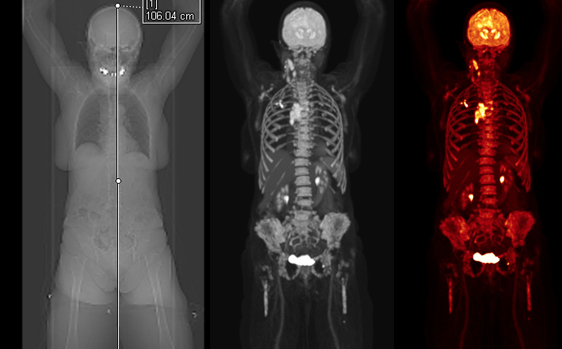

这就是目前全世界最先进的超级扫描仪:西门子Quadra PET和CT扫描机。墨尔本Theranostic创新中心引进了澳洲私人机构中的第一台!这台价值1300万澳币的扫描仪,让医生可以看到病人全身上下任何微小的异常,及时发现肿瘤。

澳洲医学教授Rod Hicks说,这台扫描仪将彻底改变癌症患者的人生。不论是心脏、肺、大脑,还是其他所有的器官,只要有异常,在这台扫描仪面前一览无余。